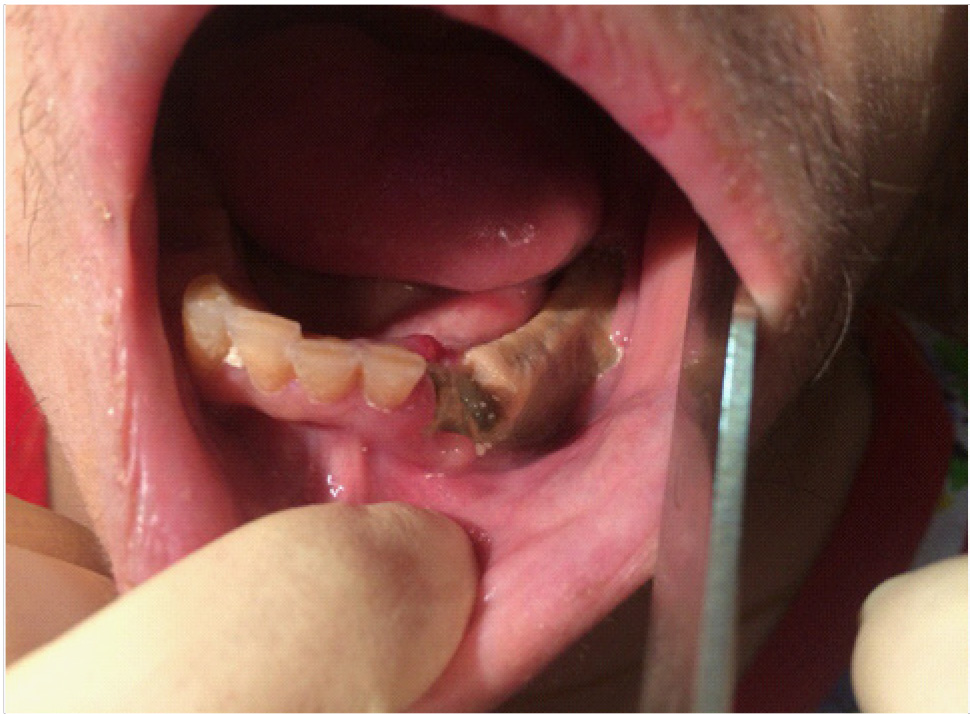

В полости рта: лунки 3.2, 3.3 зубов в субтотальном остеонекрозе альвеолярной части нижней челюсти слева. На слизистой оболочке альвеолярной части нижней челюсти справа определяется язва размером до 1,0 см с инфильтрированными краями, дно язвы выполнено некротическими массами (рис. 7).

Рис. 7. Клинические проявление бисфосфонатного остеонекроза нижней челюсти слева

Объективные данные обследования. Общее состояние на момент осмотра удовлетворительное. Конфигурация лица изменена за счет послеоперационных явлений. Определяется послеоперационная рана с гнойно-воспалительными явлениями. Определяются явления лучевого остеонекроза нижней челюсти справа (рис. 9–11). Открывание рта ограничено, умеренно болезненное. Лечение на амбулаторном этапе заключалось в активной санации гнойно-некротических проявлений в раневой поверхности, активное орошение антисептическими растворами, протеолитическими ферментами. Активная антибактериальная, противовоспалительная, симптоматическая терапия.

Рис. 9. Клинические проявления лучевого остеонекроза нижней челюсти справа

Рис. 10. Клинические проявления лучевого остеонекроза нижней челюсти справа на этапе лечения

Рис. 11. Клинические проявления лучевого остеонекроза нижней челюсти с развитием патологического перелома нижней челюсти справа

На 10-е сутки от начала лечения пациента на амбулаторном этапе на фоне снижения гнойно-некротических явлений в ране пациент обратился к врачу – стоматологу-хирургу с жалобами на патологическую подвижность нижней челюсти справа в проекции очага лучевого остеонекроза. При осмотре диагностирован патологический перелом нижней челюсти справа, пациент госпитализирован в отделение челюстно-лицевой хирургии для дальнейшего лечения.